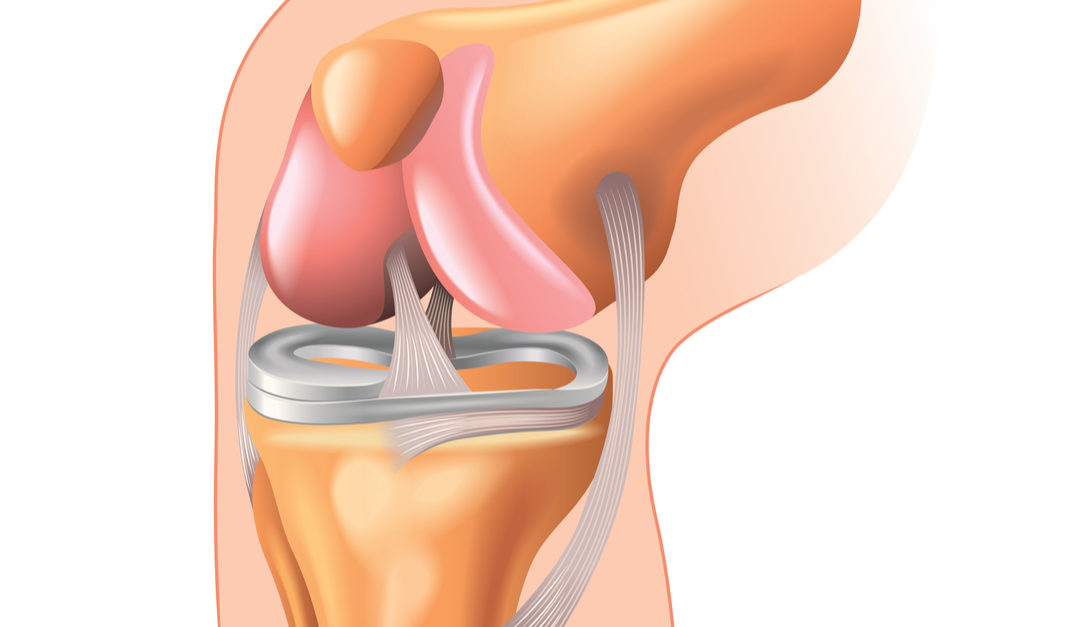

For end-stage OA (KL Grade IV) with bone-on-bone contact, significant deformity, and failure of all conservative treatments, total knee arthroplasty (TKA) or unicompartmental knee replacement (UKR) restores anatomy and dramatically improves quality of life. Surgical outcomes are now excellent modern implants have a 95% 15-year survival rate.